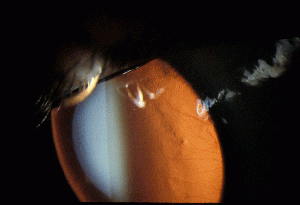

Defined narrowly, interstitial keratitis is any non-ulcerating inflammation of the corneal stroma without the involvement of either the epithelium or endothelium. Practically, however, the term refers to a common endpoint for a number of diseases which primarily manifest as inflammation and vascularization of the corneal stroma with minimal loss of tissue. Diseases that also involve other layers of the cornea secondarily are also included as long as the stroma is the predominant layer affected. The underlying causes of interstitial keratitis can broadly be either infectious or immune-mediated. The stroma constitutes the greatest thickness of all of the layers of the cornea and is made up of specially arranged collagen fibrils that allow clear transmission of light. The inflammation and blood vessel invasion characteristic of interstitial keratitis can result in scarring of this layer resulting in decreased vision.

Intralamellar infiltration of lymphocytes with extensive neovascularization in the absence of overlying ulceration. The endothelium is unaffected in the early stages but may experience decompensation later in the course along with concomitant findings of stromal and epithelial edema. Other late findings include ghost vessel formation and corneal scarring.

Signs

- Conjunctival injection

- Corneal haze: diffuse, sectoral, central, or circumferential

- White cell infiltration without significant necrosis or suppuration

- Stromal neovascularization

- Ghost vessels when the disease is quiescent

- Lipid keratopathy

Interstitial keratitis is a clinical diagnosis based on the finding of non-ulcerative, stromal keratitis with deep stromal neovascularization.